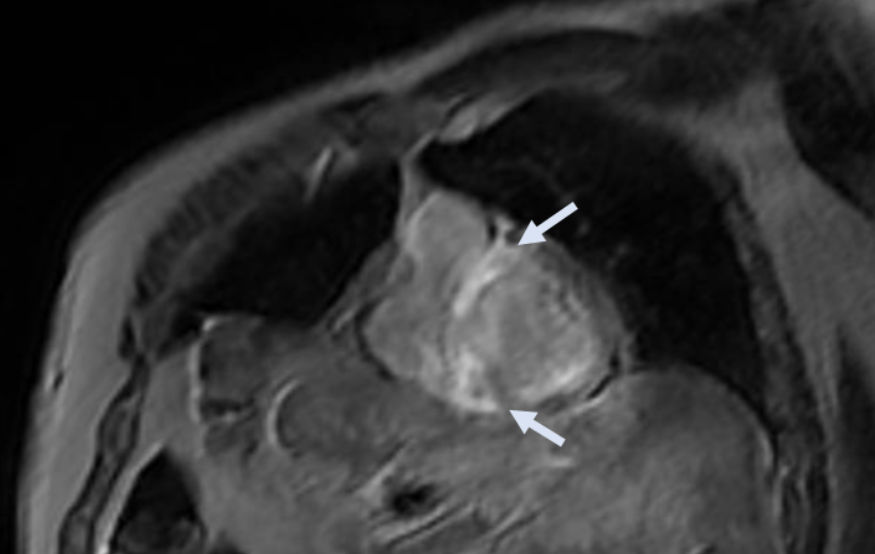

Kardiale MRT (CMR) zur weiteren Abklärung

Angesichts der elektro-anatomischen Diskordanz und des im Echokardiogramm festgestellten hypertrophen Phänotyps wurde eine CMR durchgeführt. Die Ergebnisse:

• biventrikuläre Hypertrophie mit erhaltener systolischer Funktion;

• infiltratives Muster mit ausgedehnten Bereichen von spätem Gadolinium-Enhancement (LGE) vorwiegend intramyokardial auf Höhe des basalen und mittleren Septums, der basalen postero-lateralen Wand, der Papillarmuskeln und an der subepikardial-intramyokardialen Stelle der vorderen mittleren basalen Wand und der inferioren Wand;

• Vorhandensein von LGE auch auf Höhe der Vorhofwände und des verdickten interatrialen Septums;

• außerdem Vorhandensein einer veränderten Gadoliniumkinetik, die durch eine schnelle Aufnahme des Kontrastmittels in das Myokard auf Kosten des Blutes in den Herzkammern gekennzeichnet ist.

• CMR: ventrikuläre Hypertrophie, veränderte Gadoliniumkinetik und diffuser LGE-Befund mit nicht-ischämischem Muster, der auch die Herzvorhöfe betrifft.